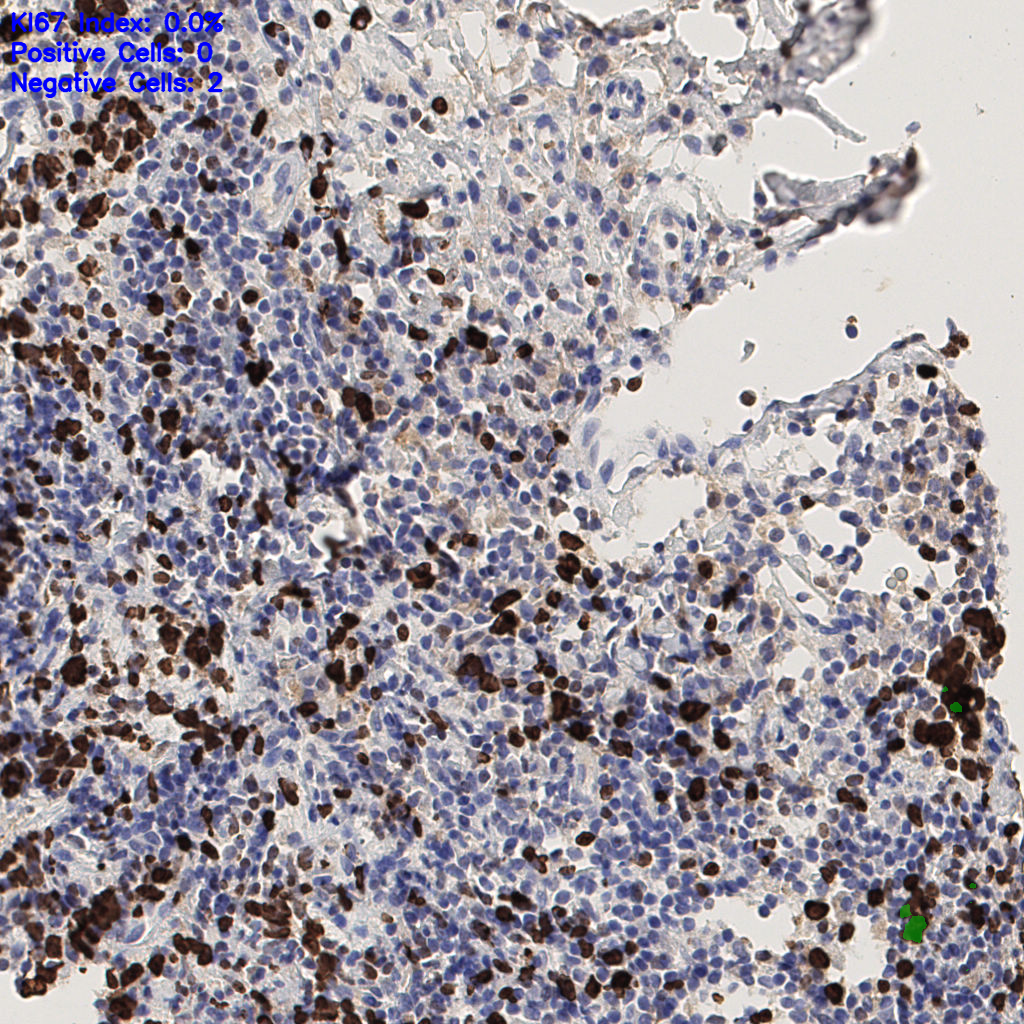

7.85%

Ki67 指数

阴 1104 阳 94

H255858-KI-67.ndpi

slice_44_7_x39424_y6272.png

slice_44_7_x39424...